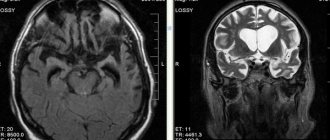

• Также применяется МРТ-исследование мозга. МРТ более эффективна при обнаружении локальных изменений. Характерные признаки атрофии — расширение борозд (кортикальная атрофия) и увеличение желудочков. На основании этого рассчитывается церебро-вентрикулярный индекс (соотношение размеров желудочков к поперечному диаметру мозга). При этой патологии на МРТ выявляется: увеличение ЦВИ; расширение субарахноидальных пространств; дегенерация белого вещества; снижение плотности ткани; уменьшение долей в размерах. На основании исследования делают количественную оценку атрофии. При генерализованной кортикальной атрофии расширение борозд и желудочков оценивается в 13 различных областях. Для определенных заболеваний характерны те или иные изменения: при болезни Пика атрофия выражена в лобной и височной области. При болезни Хаттингтона изменения головок хвостатых ядер. Болезнь Паркинсона сопровождается генерализованная атрофией и атрофией черной субстанции, а при болезни Альцгеймера — атрофия гиппокампа.